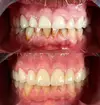

Aesthetic Dentistry

Smile Design